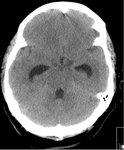

Communicating hydrocephalus in the setting of subarachnoid hemorrhage; note dilation of fourth and temporal horns of lateral ventricles

Courtesy of Dr Salah Keyrouz; used with permission